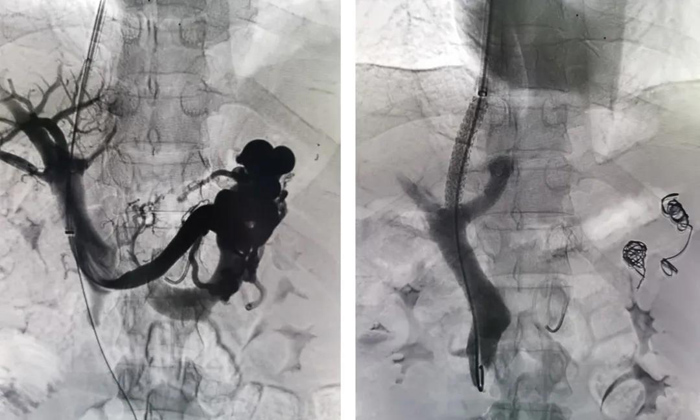

手術(shù)如期進(jìn)行,李強(qiáng)主治醫(yī)師施行此次手術(shù)。術(shù)中由頸靜脈處穿刺插管至肝靜脈,在肝實(shí)質(zhì)內(nèi)穿刺門靜脈,并植入支架,建立門靜脈與肝靜脈之間的通道;手術(shù)同時(shí)栓塞曲張靜脈,從而降低門靜脈壓力,減輕食管胃底靜脈曲張程度及出血風(fēng)險(xiǎn)。最終手術(shù)順利完成,患者和家屬臉上也露出了滿意的微笑。

TIPS技術(shù)用于治療門脈高壓癥,尤其是對(duì)因門脈高壓所致的嚴(yán)重并發(fā)癥,如上消化道出血、頑固性腹水和脾功能亢進(jìn)所致的持續(xù)性白細(xì)胞與血小板低下具有確切療效。TIPS 對(duì)肝硬化伴食管靜脈曲張破裂出血患者止血分壓起到重要的作用,對(duì)防止肝硬化食管胃底靜脈曲張破裂出血的復(fù)發(fā)具有明顯的效果。經(jīng)典的開腹門體分流術(shù)有著較高的手術(shù)死亡率,同時(shí)受到手術(shù)高危因素(高齡、心腦血管疾患、腹水、肝腎功能不良、消耗性體質(zhì)等)的限制。我院血管外科成功開展此項(xiàng)技術(shù),無疑為前來我院就診的門脈高壓患者提供更多可選的治療方法。